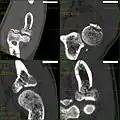

CT scan showing a radial head fracture -